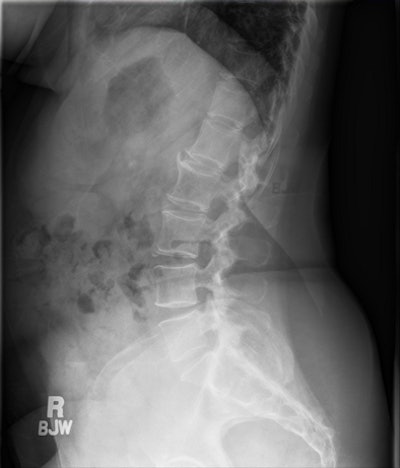

![]() |

| Outline of the patient's neckline and lead marker from a swimmer’s view of a shoulder study are seen (with inverse opacity) in this lumbar spine image taken two minutes later. The most visible artifact is directly posterior to the lumbar spine. All images courtesy of Alisa Walz-Flannigan, PhD. |

Highly opaque objects depicted in a DR image will reappear less densely in one or more subsequent images. Lag artifacts typically do not appear in images acquired 60 seconds after their onset, but intense opacities did persist sporadically for up to 15 minutes after image acquisition on a particular DR unit at Mayo because of a manufacturer's unsuccessful attempt to use a subtraction technique to eliminate the phenomenon.